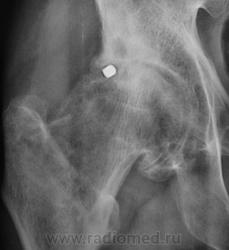

Почему-то на ум пришло сразу "Вот пуля пролетела ,и ага..".

это вероятно и есть состояние после огнестрельного ранения в виде ДОА 3 ст, инородное тело или нет?

Для точной локализации пули нужна попендикулярная ( как в "Двух капитанах" - палочки должны быть попендикулярны) проэкция. Может и не причина артроза?

Продолжение.

Да, Вы правы. Пациент желает "поставить" искусственный сустав.